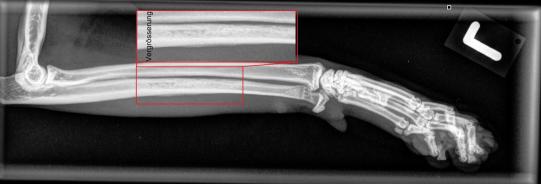

Leider erfüllt sich die Hoffnung, dass es sich nur um eine harmlose Verstauchung handelt, nicht - eine Woche später lahmt Barolo immer noch. Nun kann aber festgestellt werden, dass die Katze im mittleren Bereich des Unterarms schmerzhaft ist, weshalb die Region geröntgt wird: Die Elle ist in diesem Bereich fleckig verändert, was auf eine beginnende Auflösung des Knochens hinzuweisen scheint. Es ist zu befürchten, dass es sich um einen Knocheninfekt handelt, welcher sich Barolo bei einem Kampf zugezogen hat. Alternativ käme noch ein Befall mit Knochenkrebs in Frage, was aufgrund des Alters des Katers doch sehr unwahrscheinlich erscheint.

Zwei Wochen später hat sich die Schmerzhaftigkeit nur unwesentlich verbessert; im Röntgen erscheint die Veränderung trotz Antibiotikum sogar eher verstärkt. Könnte es tatsächlich sein, dass es sich um Knochenkrebs handelt? In diesem Fall müsste die Diagnose mittels Knochenbiopsie gestellt werden und im schlimmsten Fall das Bein amputiert werden. Vorerst entscheiden wir uns aber, die Antibiotikumtherapie um ein zweites Präparat aufzustocken und so die Behandlung zu intensivieren.

Zwei weitere Wochen später können wir endlich aufatmen und das Bein wird erneut geröntgt. Barolo geht es nun viel besser, er zeigt keine Schmerzen mehr, und auch die Röntgenaufnahme zeigt, dass sich die Veränderungen langsam zurückzubilden scheinen. Ganz offensichtlich hat es sich hier tatsächlich um einen (wohl durch einen Katzenbiss verursachten) bakteriellen Infekt der Elle gehandelt.